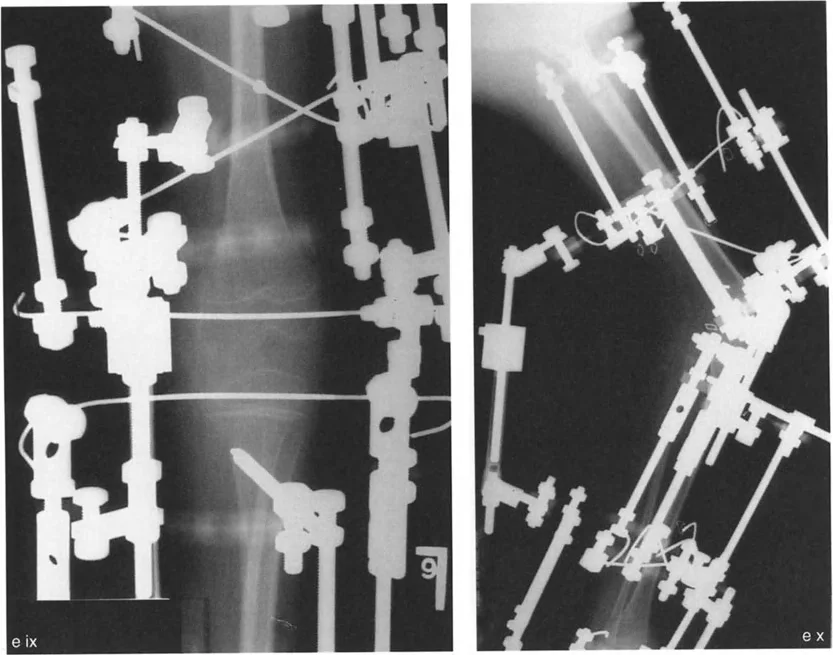

- الأشعة الجانبية الطويلة للطرف السفلي بالكامل أثناء الوقوف في أقصى بسط (Standing Long-Leg Lateral View in Maximum Extension): تُستخدم لتقييم تحدد حركة الركبة (FFD) والركبة الارتدادية (Recurvatum)، وتحديد ما إذا كان التشوه عظميًا أو ناتجًا عن تقلص في الأنسجة الرخوة.

يتم تثبيت العظام بعد القطع باستخدام صفائح ومسامير أو تثبيت خارجي، لضمان التئام العظم في الوضعية الجديدة.

- التصحيح التدريجي: في حالات تحدد الحركة الشديدة أو المعقدة، قد يكون التصحيح التدريجي باستخدام التثبيت الخارجي هو الخيار الأكثر أمانًا.

- إذا كان التشوه عظميًا (تقوس خلفي)، يتم إجراء قطع عظم انثنائي في عظم الفخذ أو الساق لتصحيح الارتدادية.